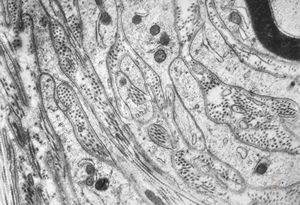

F,50y. | progressive multifocal leukoencephalopathy- viral particles in a glial cell